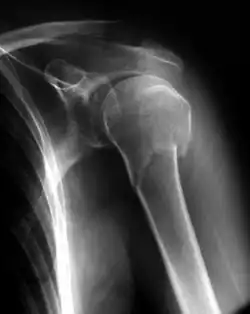

Ruhigstellung in einfachem Verband

Für einige Frakturen genügt die Ruhigstellung (Immobilisierung) mit einfachem Verband. Ein typisches Beispiel ist die nicht oder wenig verschobene, einfache Fraktur des proximalen Oberarmes: Hier genügt die Ruhigstellung im Gilchrist- oder Desault-Verband für etwa 14 Tage, dann wird rasch zur funktionellen Therapie übergegangen. Ein weiteres Beispiel sind die Frakturen der Zehen II–V: Ein sogenannter Pflasterzügelverband fesselt den verletzten Zeh an seinen gesunden Nachbarn. Auch einfache Fingerfrakturen können so behandelt werden. Ein etwas abweichendes Beispiel ist die Behandlung der Schlüsselbeinfraktur im Rucksackverband: Hier sorgt die „Erinnerungsfunktion“ des Verbandes dafür, dass der Verletzte seine Schulter nach hinten zieht und somit einer Verkürzung der Fraktur entgegenwirkt.